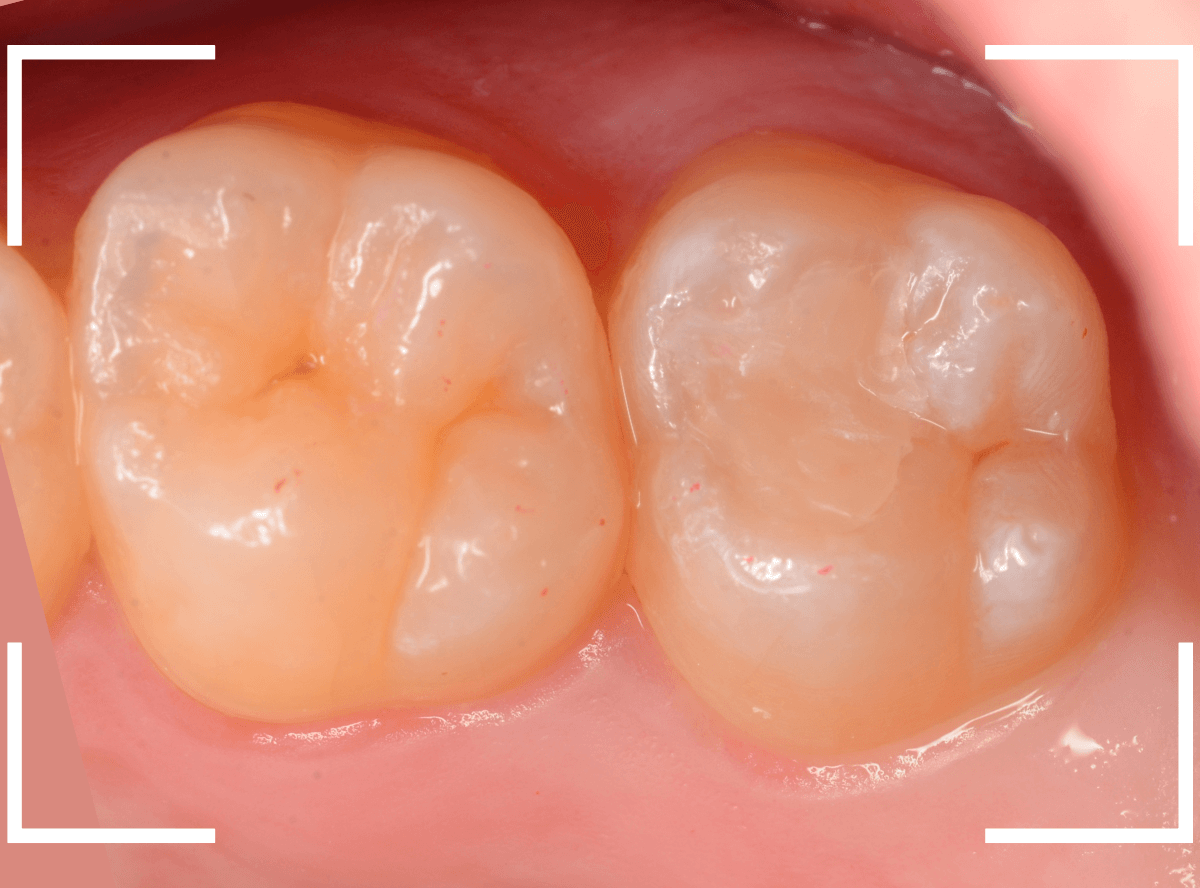

両歯とも、虫歯を全て除去したところです。

歯の溝から、かなり虫歯が広がっている状態でした。

全ての虫歯を除去したところです。

写真ではわかりづらいですが、かなり深く、神経の近くまで虫歯は進行していました。

全ての虫歯を除去しました。

奥歯は、レントゲン所見とおり、かなり深い虫歯でした。

最終setした状態です。

set後も症状なく、患者さんにも、満足していただける仕上がりになりました。